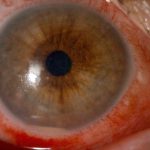

Kocaeli’nde yaşayan 52 yaşında kadın, iddiaya göre uzağı görememesi sebebiyle kullandığı gözlükten kurtulmak için yaklaşık 7 ay önce kırlangıç otunun suyunu gözlerine damlattı ve bir anda göremez hale geldi. Önce gözlerinde yanma, batma hisseden ve sonrasında açamaz hale gelen kadın hemen hastaneye koştu. O dönem Kocaeli’nde çalışan Göz Hastalıkları Uzmanı Doç. Dr. Ömer Faruk Yılmaz ve ekibi hastaya müdahale ederken korneanın en dış katmanı olarak ifade edilen kornea epitelinin zarar gördüğü belirlendi. Göze yabancı cisim, kimyasal madde kaçması ya da enfeksiyon durumlarında gözü temizlemek amacıyla uygulanan göz yıkama tedavisi gerçekleştirildi. Yaklaşık 2 haftalık tedavinin ardından hasta sağlığına kavuştu. Doç. Dr. Yılmaz, hastasının yaşadığı süreç ve tedavisine ilişkin bilgi verdi. Yılmaz, hekim önerisi olmadan herhangi bir ürün kullanılmaması gerektiğine dikkat çekerek önemli uyarılarda bulundu. Öte yandan hastanın göz bebeğinin beyazlığı ve göz akının ise kızardığı hali fotoğraf karesine yansıdı.

Hastasına ilişkin bilgi veren Doç. Dr. Ömer Faruk Yılmaz, “52 yaşında bir bayan hastamız, kızının önerisiyle gözlükten kurtulmak için 2 gözüne taze kırlangıç otu suyunu sıkarak damlatmıştı. Kırlangıç otunu sıktığımız zaman sarı bir sıvı akmaktadır. Hastamız o sıvıyı her 2 gözüne damlatmış. İlk aşamada gözünde yanma, batma oluyor, birkaç saat sonra her 2 gözünü açamıyor, tamamen göremez hale geliyor. Bize geldiğinde hastamız 2 gözünü açamaz haldeydi. Göz muayenesinde 2 gözün korneasının tamamen tahrip olduğunu gördük. Korneanın epiteli tamamen soyulduğu için hastamızın gözünde pü şeklinde akıntı mevcuttu. Hasta, ‘Acaba göremeyecek miyim, gözüme ne oldu, bu ilacı neden damlattım?’ diye sorgulayarak gelmişti” dedi.

“Kırlangıç otu kullandı, hastamız göremez hale geldi eğer tedavi edilmeseydi sonucun ne olacağını bilemiyoruz fakat tedavi sonucunda hastamız iyileşti. Gözlerinin fotoğrafını çektirdim, kırlangıç otunun geçişini gösterdik. Tedavi edilmediği zaman göz içinde belki de körlüğe ulaşabilecek şekilde istenmeyen yan etkilere yol açabilir. Yüzlerce farklı ot olabilir, yanlışlıkla faydalı bir ot damlatacağız diye zararlı bir otu damlatabiliriz. Göze direkt damlatılması steril değildir, göze zarar verebilir, enfeksiyon oluşturabilir. Faydalı bile olsa Sağlık Bakanlığı ruhsat vermeden, ilaç formatına dönüştürmeden, uygun dozajlar ayarlanmadan ve göz hekiminin önerisi olmadan göze herhangi bir bitkisel ilaç damlatılmasını önermiyoruz.”